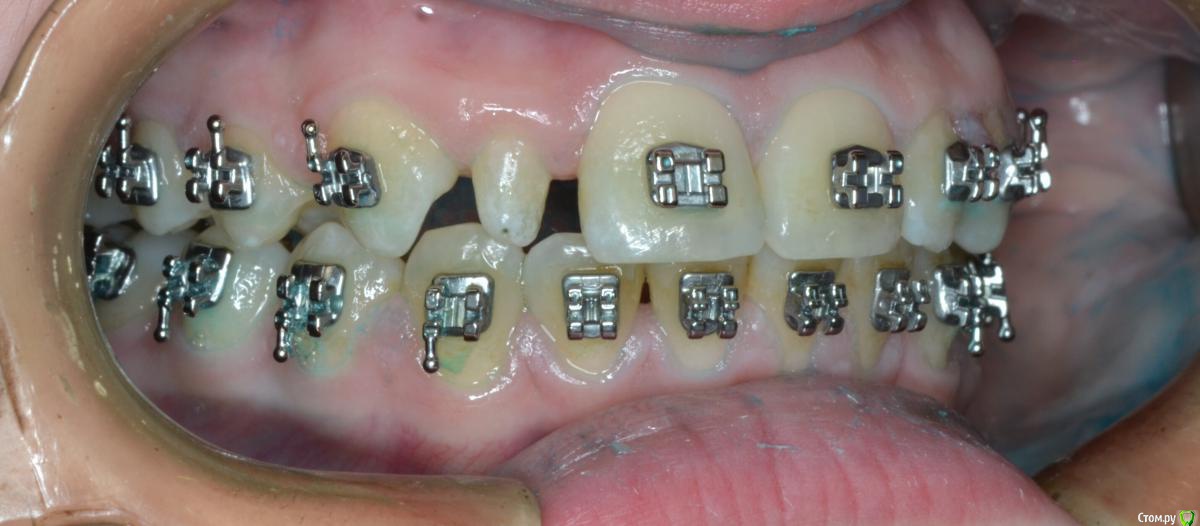

CRAZYDUCK Опубликовано 20 мая, 2018 Автор Поделиться Опубликовано 20 мая, 2018 Шиповидный боковой резец 1.2 . Изначально был дефицит места . Место создали -зуб восстановили ( реставрация временная - на время ортодонтического лечения , после полноценная реставрация). 1 Ссылка на комментарий